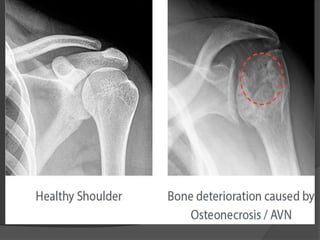

Late stage (ARCO 4)

 Secondary arthritic lesion (calcification

+resorptive cyst).

 Deformity

 Detect by any imaging method.

Most common sites

 Head of humerus

Late stage (ARCO4)  Secondary arthritic lesion (calcification +resorptive cyst).  Deformity  Detect by any imaging method.